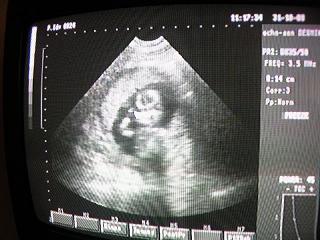

Már bizti hogy kislány, mert ma reggel voltunk genetikain és itt is megerősitették! hááát mit mondjak nem sok minden van rajta:

egy élő magzat, lepény mellől

BPD 46mm, THQ 44mm, FL29mm

átlagos mennyiségű magzatviz

fejlődési rendellenesség nem látható

Dg Grav s 18

hát ennyi...a 4D-n ennél többet méricskélt a nő. de hát ha hajdú krisztina nem látott rosszat, akkor csak ok minden! nem hiszem hogy megyünk most 4D-re, majd kicsit később mikor már pufókabb lesz, és mosolyog meg szép lesz az arca is! (apa megint mondott valami hülyeséget mikor odaértünk az uh-ra, és ott össze is vesztünk...majdnem haza is zavartam, hogy hagyjon békén. utána meg most bújik hogy semmi nem történt. de örült mikor megint hallotta hogy kislány. ekkor elfelejtettem a vitát is. ő a legfontosabb, és az hogy minden ok vele)